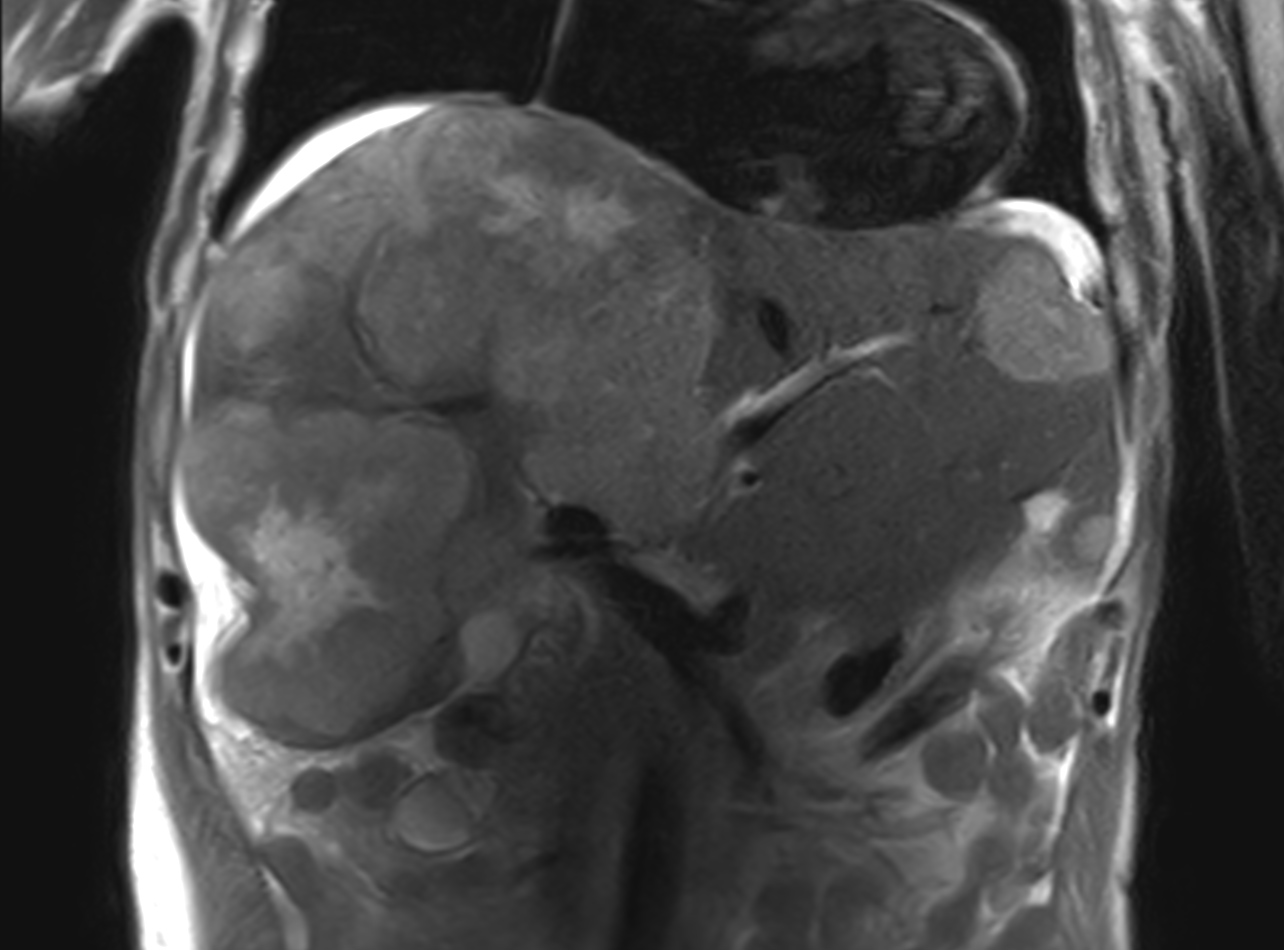

Patient with liver metastasis. The ExamCard includes techniques for efficient fat-free imaging over large field-of-views (mDIXON XD), a procedure for non-invasive liver fat quantification (mDIXON Quant), a multi-phase contrast-enhanced sequence (4D FreeBreathing) to improve imaging confidence and Compressed SENSE to accelerate the entire exam.

T2w TSE